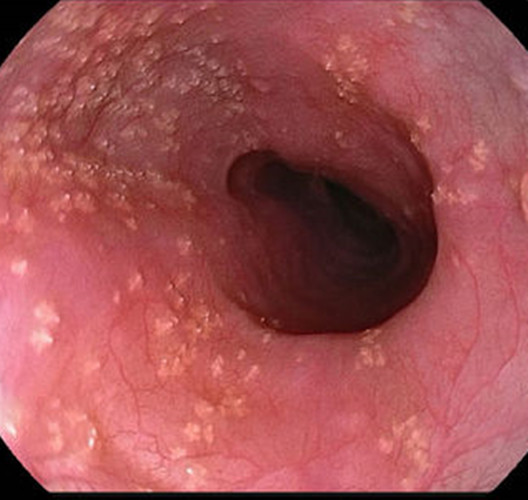

消化道白色念珠菌感染

咽喉白色念珠菌感染